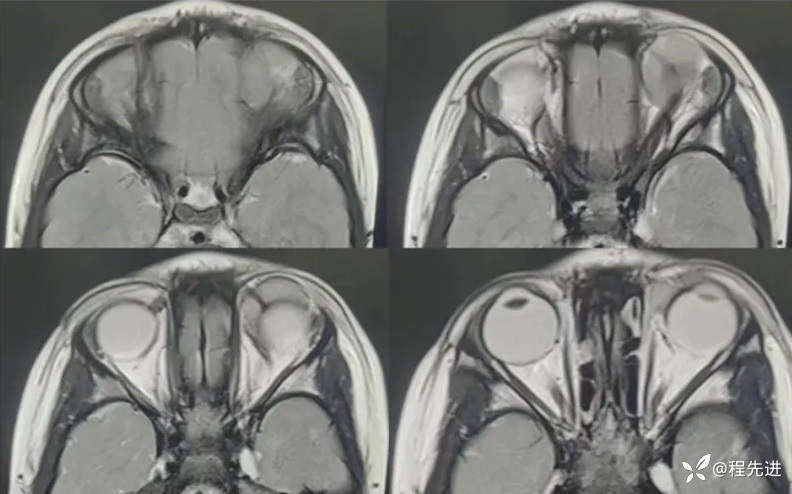

MRI平扫+增强:

T2:

T1:

FLAIR:

T1增强: